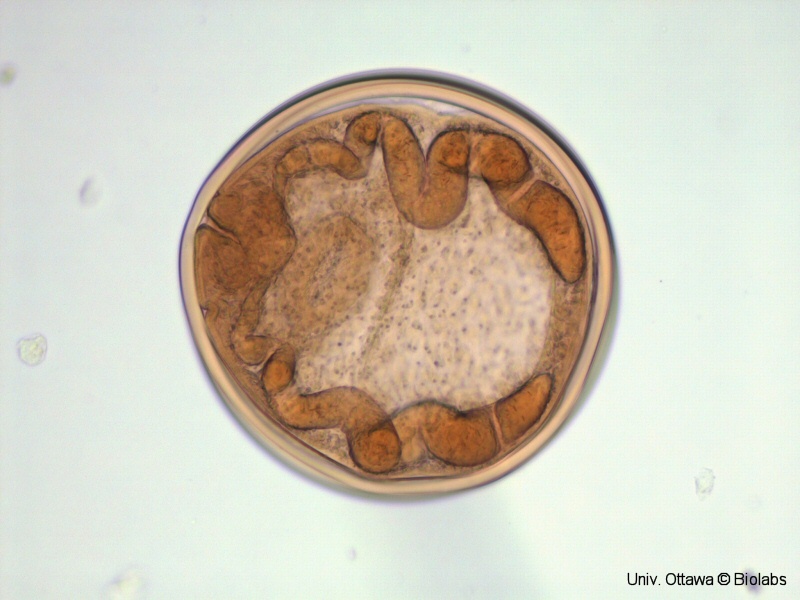

Paragonimus westermani

Japanese lung fluke or oriental lung fluke / douve orientale du poumon

whole mount (EN) / montage entier (FR)

Species (EN) / Espèces (FR) : Paragonimus westermani

(EN) : Life stage: Encysted metacercaria containing a developing juvenile fluke.

(FR) : Stade de vie : Métacercaire enkystée contenant une douve juvénile en développement.